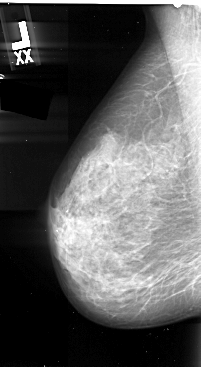

A_1058_1.LEFT_MLO

LEFT_CC LINES 4951 PIXELS_PER_LINE 2836 BITS_PER_PIXEL 16 RESOLUTION 42 NON_OVERLAY